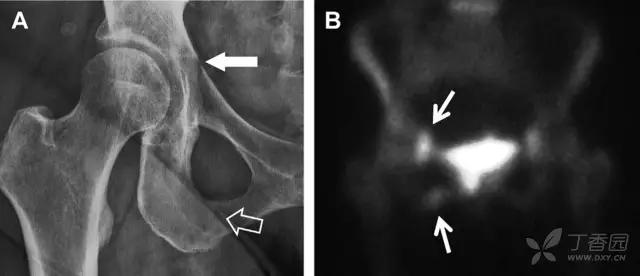

髋臼骨折最常见的类型是髋臼后壁骨折,几乎占髋关节骨折的 1/4,且常常合并髋关节后脱位。由于骨性结构重叠,可能肉眼看上去觉得非常轻微的骨折,事实却并非如此。髋臼后缘中断常常是髋臼后壁骨折的一个特征(图 2)。

图 2 为髋臼后壁骨折伴髋关节脱位患者。A 右侧髋关节 X 线片示股骨头后方可见一骨折线(箭头),髋臼后缘中断。B 左侧髋关节 X 片对照可见髋臼后缘连续(箭头)。C CT 三维重建图像示髋臼后壁缺损,可见旋转、移位的骨折块(箭头)